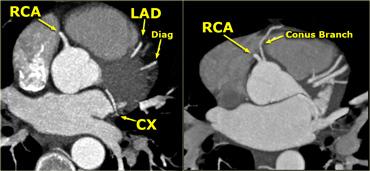

Động mạch vành phải (RCA)

Động mạch vành phải xuất phát từ xoang Valsalva trước và đi qua rãnh nhĩ thất phải (AV) giữa nhĩ phải và thất phải đến phần dưới của vách liên thất.

Trong 50-60% trường hợp, nhánh đầu tiên của RCA là nhánh nón nhỏ, cấp máu cho đường ra thất phải.

Trong 20-30% trường hợp, nhánh nón xuất phát trực tiếp từ động mạch chủ.

Trong 60% trường hợp, động mạch nút xoang xuất phát như là nhánh thứ hai của RCA, chạy ra sau đến nút xoang nhĩ (trong 40% trường hợp nó xuất phát từ Cx).

Các nhánh tiếp theo là một số nhánh chéo chạy ra trước để cấp máu cho thành trước của thất phải.

Nhánh bờ cấp lớn (AM) tách ra với góc nhọn và chạy dọc theo bờ của thất phải phía trên cơ hoành.

RCA tiếp tục đi trong rãnh nhĩ thất ra phía sau và cho một nhánh đến nút nhĩ thất.

Trong 65% trường hợp, động mạch liên thất sau (PDA) là một nhánh của RCA (tuần hoàn ưu thế phải).

PDA cấp máu cho thành dưới của thất trái và phần dưới của vách liên thất.

Trên hình ngoài cùng bên trái, chúng ta thấy tình huống phổ biến nhất, trong đó RCA xuất phát từ lá van vành phải và sẽ cho nhánh nón ở mức thấp hơn (không hiển thị).

Trên hình kế bên, chúng ta thấy một nhánh nón xuất phát trực tiếp từ động mạch chủ.

Nhánh bờ cấp lớn (AM) cấp máu cho thành bên của thất phải.

Trong trường hợp này có tuần hoàn ưu thế phải, vì động mạch liên thất sau (PDA) xuất phát từ RCA.